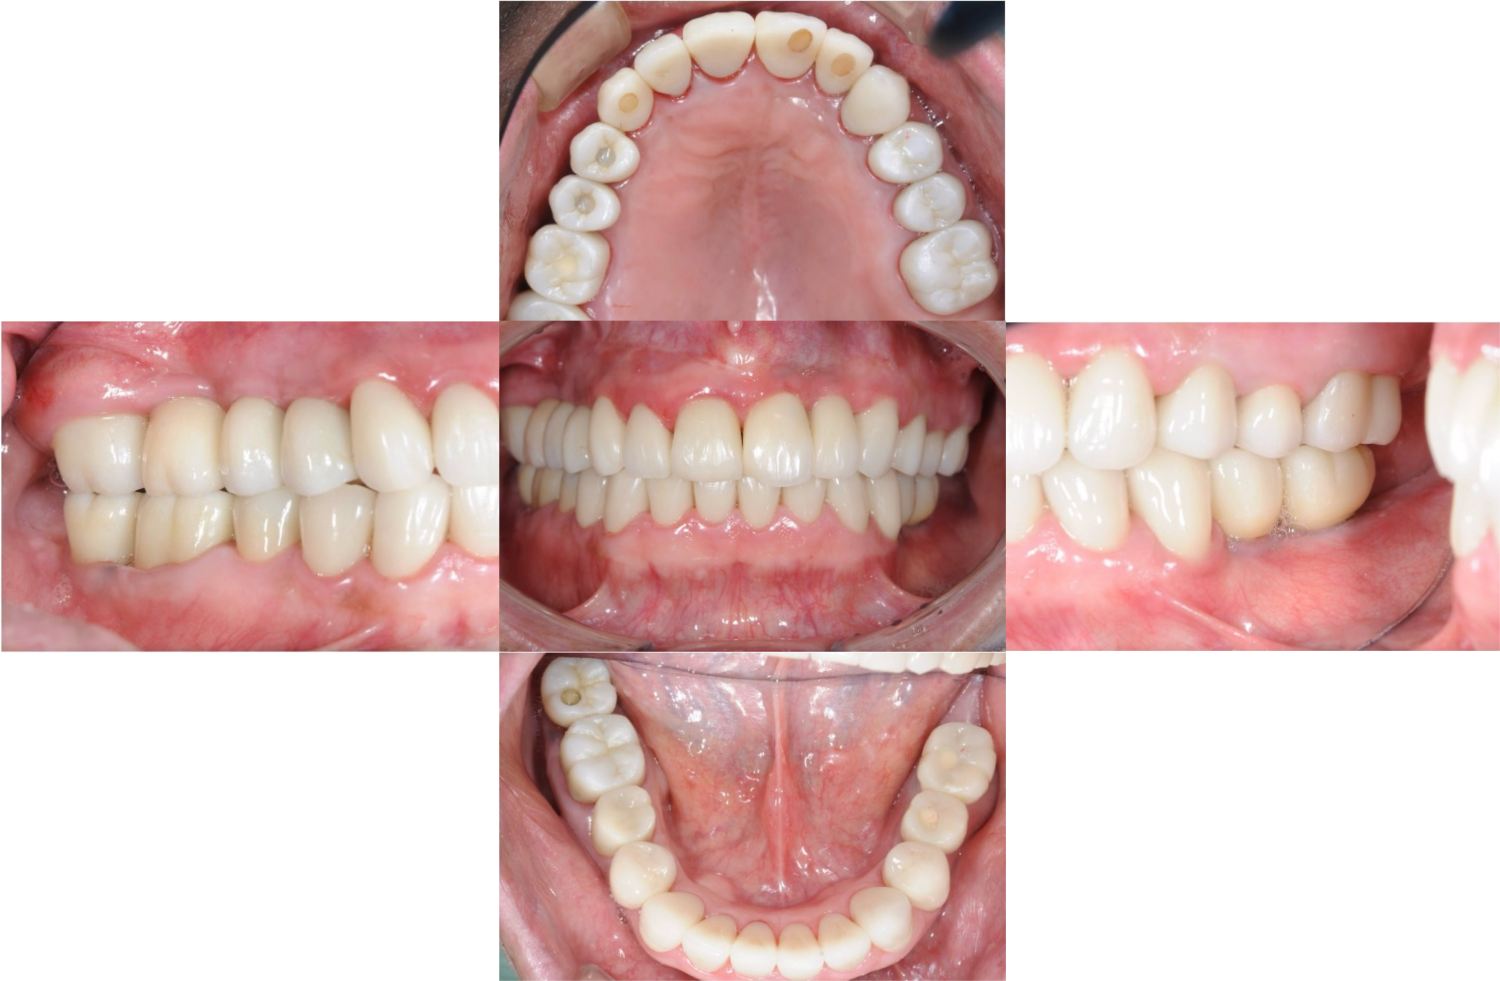

下顎臼歯部が欠損した患者さんのインプラント治療の症例②(うえだ歯科)

| 主訴 | 全顎治療希望、下の奥の歯が無いので全く噛めない。綺麗で噛めるようになりたい |

| 治療内容 | 下顎臼歯部欠損放置のため、臼歯部においてスペースがないため、全顎治療を行い咬合再構成を行う。 早期においてインプラント治療、咬合関係を模索した後、全顎にわたりセラミックによる補綴治療、その後メインテナンスに移行 |

| 治療費 | 5,410,000円(税込)(インプラントすべて含む) |

| 治療期間 | 1年8ヶ月 |

| 治療回数 | 80回 |

| 想定されたリスク | 食いしばり(パラファンクション)によるセラミックの破折、歯の破折 |